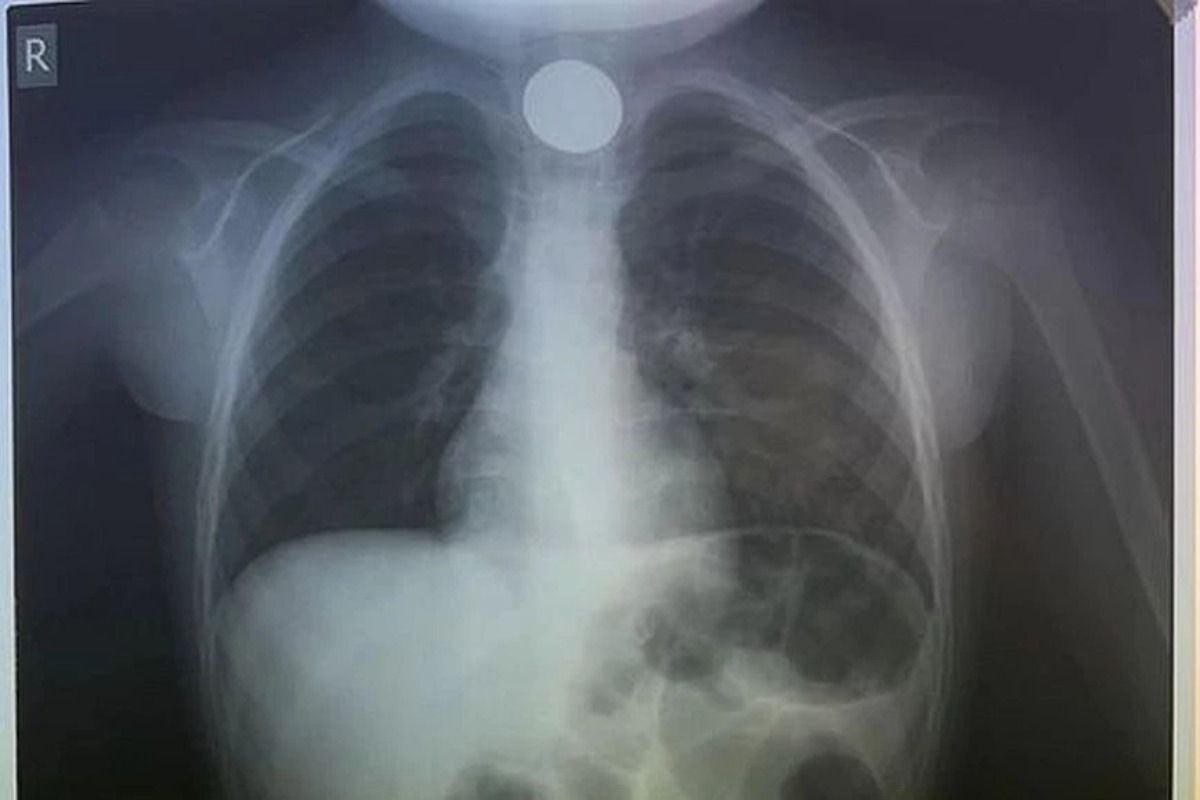

Όταν έφτασαν στο ΠΑΓΝΗ, η πρώτη κίνηση των γιατρών ήταν να του κάνουν ακτινογραφία, για να δουν σε ποιο σημείο ακριβώς είχε σταθεί το νόμισμα και αμέσως μετά προχώρησαν στη διαδικασία αφαίρεσής του. Δεν πέρασε πολύς χρόνος και οι γιατροί κατάφεραν να αντιμετωπίσουν επιτυχώς το επείγον περιστατικό, λύνοντας ταχύτατα το πρόβλημα.